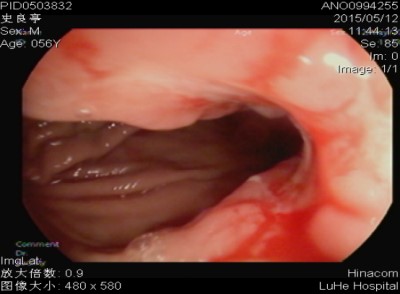

三、大肠癌

大肠癌好发年龄一般在50~70岁,男性比女性多。大肠癌的致病原因尚不明确。大肠癌的早期信号:(1)粪便带鲜血,(2)持续或反复发作的脓血便,有排不尽感觉,(3)排便习惯改变,超过3周应注意。(4)大便形状改变,变细、变扁或有槽沟。(5)出现贫血,粪便检查反复多次或持续出现隐血者。(6)持续性下腹部不适、腹部肿块、体重减轻。